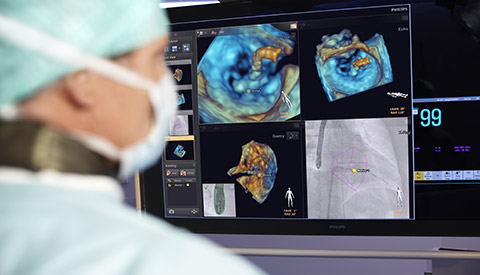

تشهد حاليًا خيارات العلاج التي لا تتطلب سوى تدخل جراحي محدود في القلب والأوعية الدموية انتشارًا ملحوظًا. ولقد ساهمت التطورات الأخيرة في مجالات التشخيص والتوجيه بالصور المباشرة Live Image Guidance والمعلوماتية في جعل هذا الأمر ممكنًا. بالتعاون مع أشهر أطباء أمراض القلب، ابتكرنا حلولاً تساهم في منح المرضى الفرصة لتغيير حياتهم. فهذه الحلول تساعد في تسريع سير العمل وزيادة فعالية الطاقم الطبي وتوفير أفكار سريرية.

معًا، سنغير طريقة تقديم الرعاية وسنحسّن نوعية حياة مرضى القلب والأوعية الدموية.

تعلّم كيف تستطيع الحلول التي ابتكرناها في مجال طب القلب مساعدة مؤسستك